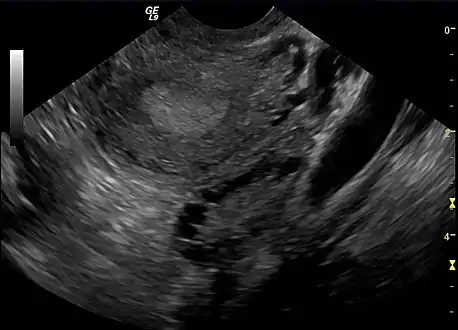

Polycystic ovary as seen on sonography

The syndrome acquired its most widely used name due to the common sign on ultrasound examination of multiple (poly) ovarian cysts. These "cysts" are in fact immature ovarian follicles. The follicles have developed from primordial follicles, but this development has stopped ("arrested") at an early stage, due to the disturbed ovarian function. The follicles may be oriented along the ovarian periphery, appearing as a 'string of pearls' on ultrasound examination.[86]

- Gynecologic ultrasonography, specifically looking for small ovarian follicles. These are believed to be the result of disturbed ovarian function with failed ovulation, reflected by the infrequent or absent menstruation that is typical of the condition. In a normal menstrual cycle, one egg is released from a dominant follicle – in essence, a cyst that bursts to release the egg. After ovulation, the follicle remnant is transformed into a progesterone-producing corpus luteum, which shrinks and disappears after approximately 12–14 days. In PCOS, there is a so-called "follicular arrest"; i.e., several follicles develop to a size of 5–7 mm, but not further. No single follicle reaches the preovulatory size (16 mm or more). According to the Rotterdam criteria, which are widely used for diagnosis of PCOS,[10] 12 or more small follicles should be seen in a suspect ovary on ultrasound examination.[21] More recent research suggests that there should be at least 25 follicles in an ovary to designate it as having polycystic ovarian morphology (PCOM) in women aged 18–35 years.[95] The follicles may be oriented in the periphery, giving the appearance of a 'string of pearls'.[96] If a high-resolution transvaginal ultrasonography machine is not available, an ovarian volume of at least 10 ml is regarded as an acceptable definition of having polycystic ovarian morphology. rather than follicle count.[95]

Ultrasound findings in PCOS include enlarged ovaries with peripheral follicles in a "string of pearls" configuration.